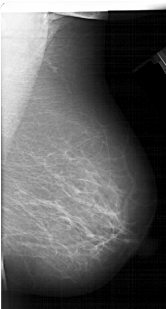

A_1324_1.RIGHT_MLO

RIGHT_MLO LINES 5551 PIXELS_PER_LINE 2986 BITS_PER_PIXEL 12 RESOLUTION 43.5 NON_OVERLAY